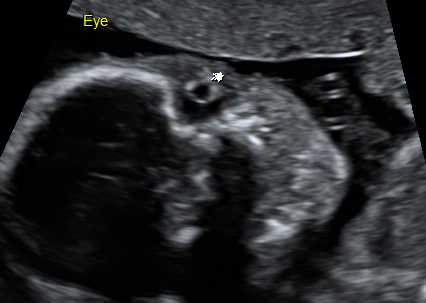

孕日記22w3d 自費高層次超音波 小芋圓心臟的小白點